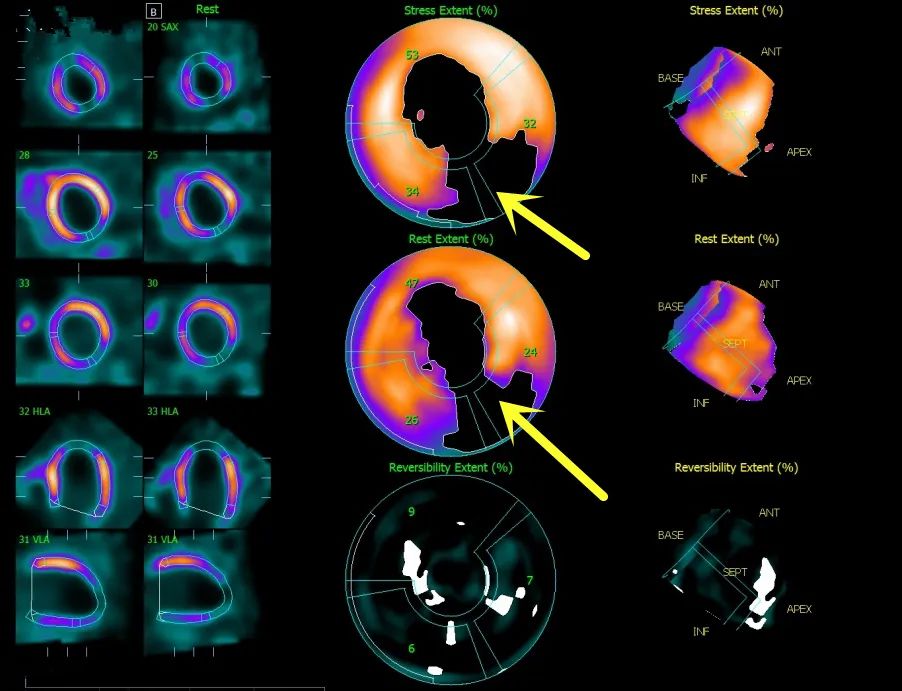

spect心肌核素对冠脉慢血流的辅助诊断及尼可地尔的疗效评估